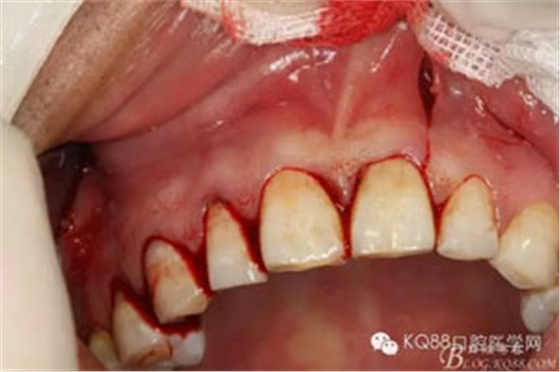

圖2.抗感染治療一周后,行11、12、13根管治療術(shù)。

圖3.局部麻醉下,行唇側(cè)21垂直切口+齦溝內(nèi)水平切口